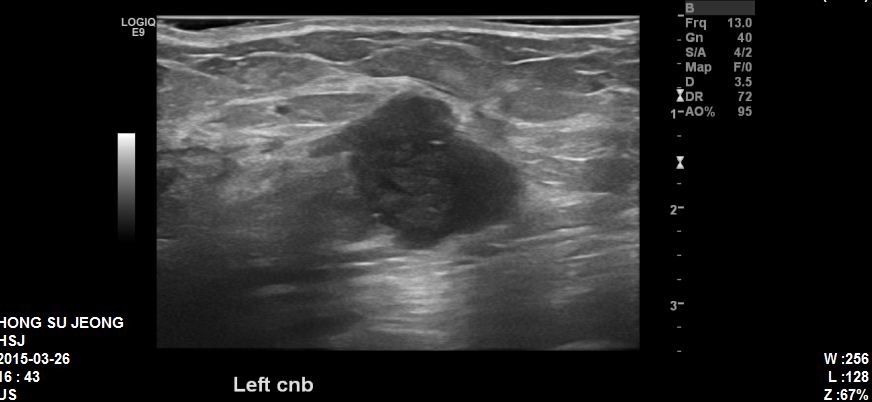

좌측유방에 만져지는 혹으로 타원 초음파후

정밀검사위해 내원하신 40대 환자분이십니다.

타원 초음파상에 좌측의 혹과 좌측겨드랑이에 림프절 비대를 확인하고

각각 조직검사와 세침검사 시행하였고

결과상 침윤성유관암 진단되었고 겨드랑이림프절 전이 확인되었습니다.